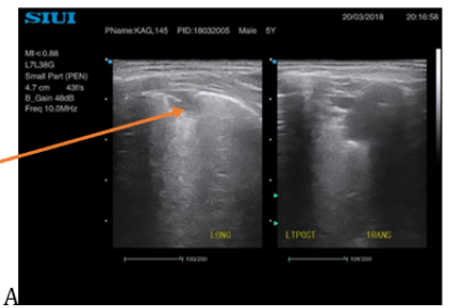

Diagnostic Performance of Chest Ultrasound in Diagnosing Pneumonia in Pediatric Patients at Mulago National Referral Hospital, Kampala, Uganda

Agnes Kyomuhangi, Daniel Atwine, Geoffrey Erem, Edison Arwanire Mworozi and Samuel Bugeza. 12(2): 03-16.